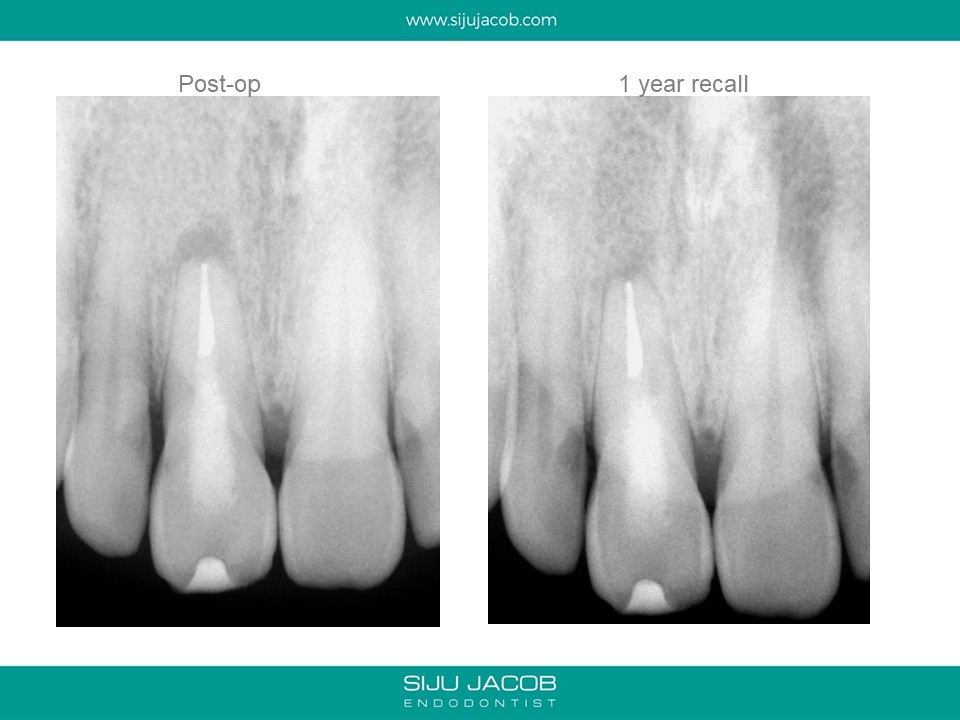

This case was referred by another practitioner who attempted to locate the canal, but couldn’t find it. The practitioner had perforated palatally in an effort to search for the canal. The perforation was supra-crestal and was sealed with Glass Ionomer. When viewed under the microscope, one can clearly see the calcified portion of what used to be the canal at one time. Once we are able to differentiate between the calcified canal and the adjacent dentine, it becomes predictable to drill apically to locate the canal.